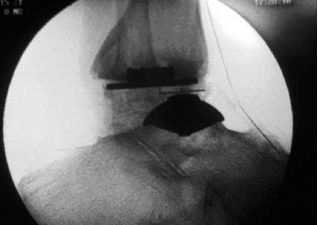

The most frequent complication of total ankle arthroplasty in the past has

been loss of bone support.

Fig 1: Talar component subsidence.

Most orthopaedic prostheses depend primarily on bone for support.

Unfortunately, however, many patients needing prosthetic arthroplasties have

weakened or compromised bone. Past experience with total ankle arthroplasty

has shown that loss of support is a primary reason for failure (Fig. 1).